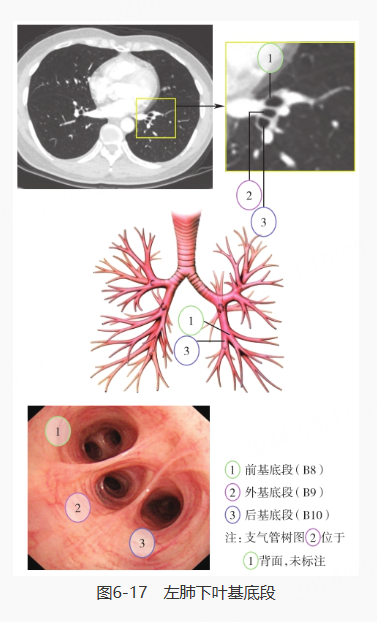

再对左肺进行探查,分别是左主支气管、左肺上叶·下叶、左肺上叶上支·舌支、左肺上叶尖后段·前段、左肺上叶上舌段·下舌段、左肺下叶、左肺下叶背段、左肺下叶基底段: